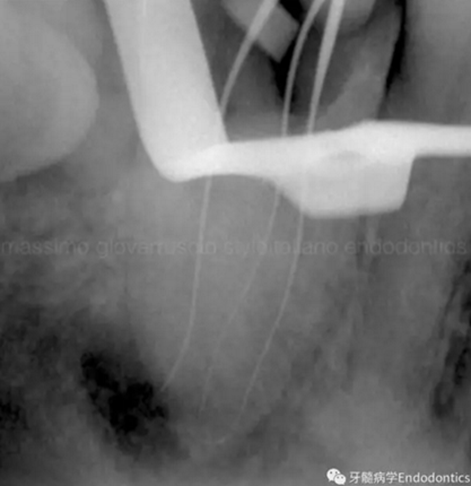

當建立直線通路、找到所有的根管口后,重心應轉移到根管預備上。若牙髓存在活力且持續(xù)滲血,應使髓室內充滿粘性螯合劑。在牙髓已壞死的情況下,應使用加熱的5.25%次氯酸鈉溶液沖洗并徹底充滿髓室。探查前,根據術前X線片測量并預彎小的不銹鋼銼,以順應預估的根管長度及彎曲度。使用0.02錐度的10號不銹鋼手用K銼探查根管冠方2/3。

圖2.疏通根管冠方2/3后,使用次氯酸鈉溶液沖洗根管,且可以使用手用器械、GG鉆(刷洗動作)、旋轉鎳鈦成形銼預敞根管。當冠方2/3進行了合適的預備且充滿沖洗液后,接著進行根尖1/3的探查以收集信息。使用小的手用銼(8號或10號K銼)疏通根管的剩余部分,確認建立了流暢的、無阻礙的、平滑的到達根尖止點的引導通道。